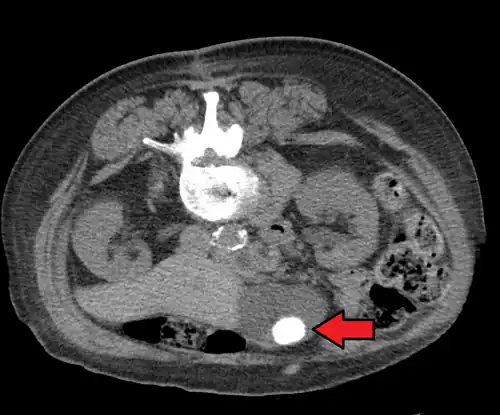

On abdominal ultrasound, sinking gallstones usually have posterior acoustic shadowing. In floating gallstones, reverberation echoes (or comet-tail artifact) is seen instead in a clinical condition called adenomyomatosis. Another sign is wall-echo-shadow (WES) triad (or double-arc shadow) which is also characteristic of gallstones.[43]

A 1.9 cm gallstone impacted in the neck of the gallbladder and leading to cholecystitis as seen on ultrasound. There is 4 mm gall bladder wall thickening.

Large gallstone as seen on CT -